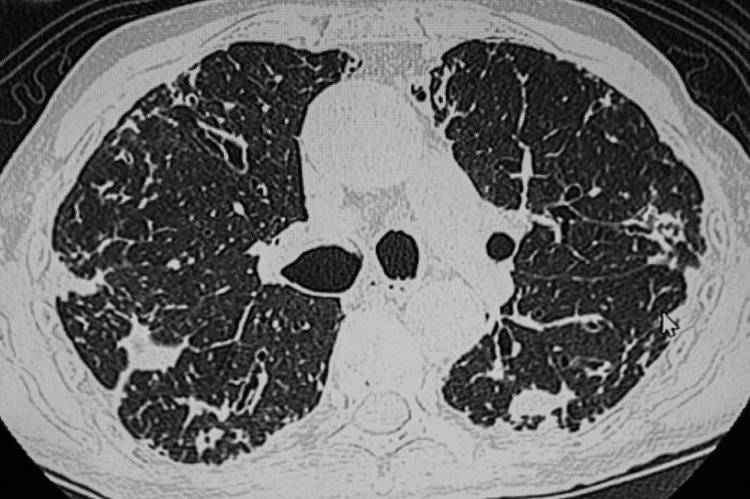

• 肺结节

肺结节是指肺部出现的≥3cm的病灶,在影像学里表现为密度增高的阴影。

中国医学科学院肿瘤医院山西医院胸外科主任廉建红指出,现在检查仪器的精密度都很高,一些微小结节也能被及时发现,这些结节发现时大部分是比较早期的,无需过分紧张。尤其是8mm以下的结节,一般都建议以随访为主。

建议年龄>45岁的成年人每年进行一次肺部CT检查,通过检查可及时发现早期潜在的问题,对防治结节有重要意义。